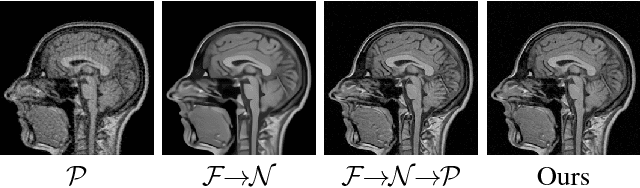

Abstract:Conventional deformable registration methods aim at solving a specifically designed optimization model on image pairs and offer a rigorous theoretical treatment. However, their computational costs are exceptionally high. In contrast, recent learning-based approaches can provide fast deformation estimation. These heuristic network architectures are fully data-driven and thus lack explicitly domain knowledge or geometric constraints, such as topology-preserving, which is indispensable to generate plausible deformations. To integrate the advantages and avoid the limitations of these two categories of approaches, we design a new learning-based framework to optimize a diffeomorphic model via multi-scale propagations. Specifically, we first introduce a generic optimization model to formulate diffeomorphic registration with both velocity and deformation fields. Then we propose a schematic optimization scheme with a nested splitting technique. Finally, a series of learnable architectures are utilized to obtain the final propagative updating in the coarse-to-fine feature spaces. We conduct two groups of image registration experiments on 3D adult and child brain MR volume datasets including image-to-atlas and image-to-image registrations. Extensive results demonstrate that the proposed method achieves state-of-the-art performance with diffeomorphic guarantee and extreme efficiency.